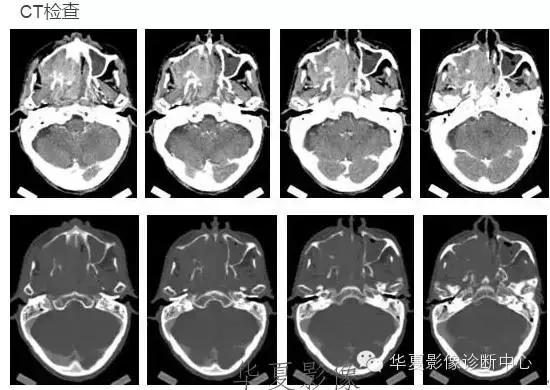

颅内黑色素瘤

中枢神经系统内原发性黑色素瘤少见, 因脑和脊髓的软脑( 脊) 膜及蛛网膜上含有黑色素细胞, 黑色素可发生于软脑( 脊) 膜的任何部位,故其发生部位常位于脑( 脊髓) 表面, 沿软脑膜生长; 而继发性黑色素瘤同一般转移性肿瘤, 常位于灰白质交界区。

影像表现:常表现为短 T1 高信号, 短T2WI 低信号,又因为黑色素瘤是富血管性肿瘤, 增强扫描常表现为明显强化。

★但少数肿瘤也不具备上述典型信号特征,主要原因是肿瘤内黑色素量多少影响。只有当黑色素瘤中黑色素细胞超过一定含量( ﹥ 10% ) 时, 才会出现黑色素瘤的典型MRI表现; 不典型的黑色素瘤因其黑色素含量较少,不足以缩短T1、T2弛豫时间,而表现为长T1低信号、长T2高信号。

依据黑色素瘤的不同 MRI 影像表现将其分为 4 种类型: ( 1) 黑色素型。该黑色素瘤因含有丰富的黑色素颗粒, MRI表现较典型,即短 T1 高信号,短 T2 低信号。( 2) 无黑色素型。因该类黑色素瘤不含黑色素颗粒或含量较低,MRI 表现为长 T1 低信号,长 T2 高信号; ( 3) 混合型。黑色素型和非黑色素型两者的混合; ( 4) 出血型。表现为血肿不同时期的信号特征, 该黑色素瘤 MRI增强扫描表现为不均匀环状或弥漫性强化